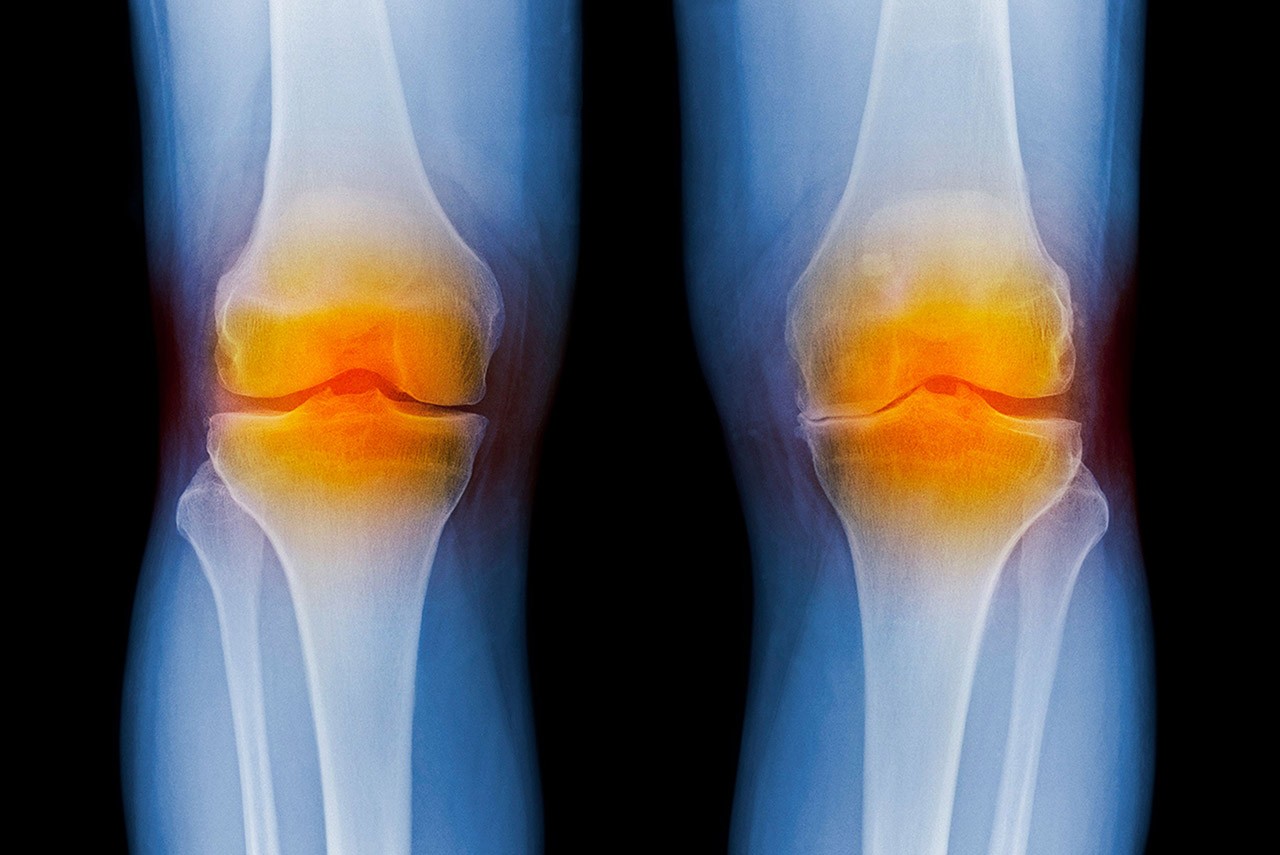

knee X-ray

PHOTO: GETTY IMAGES